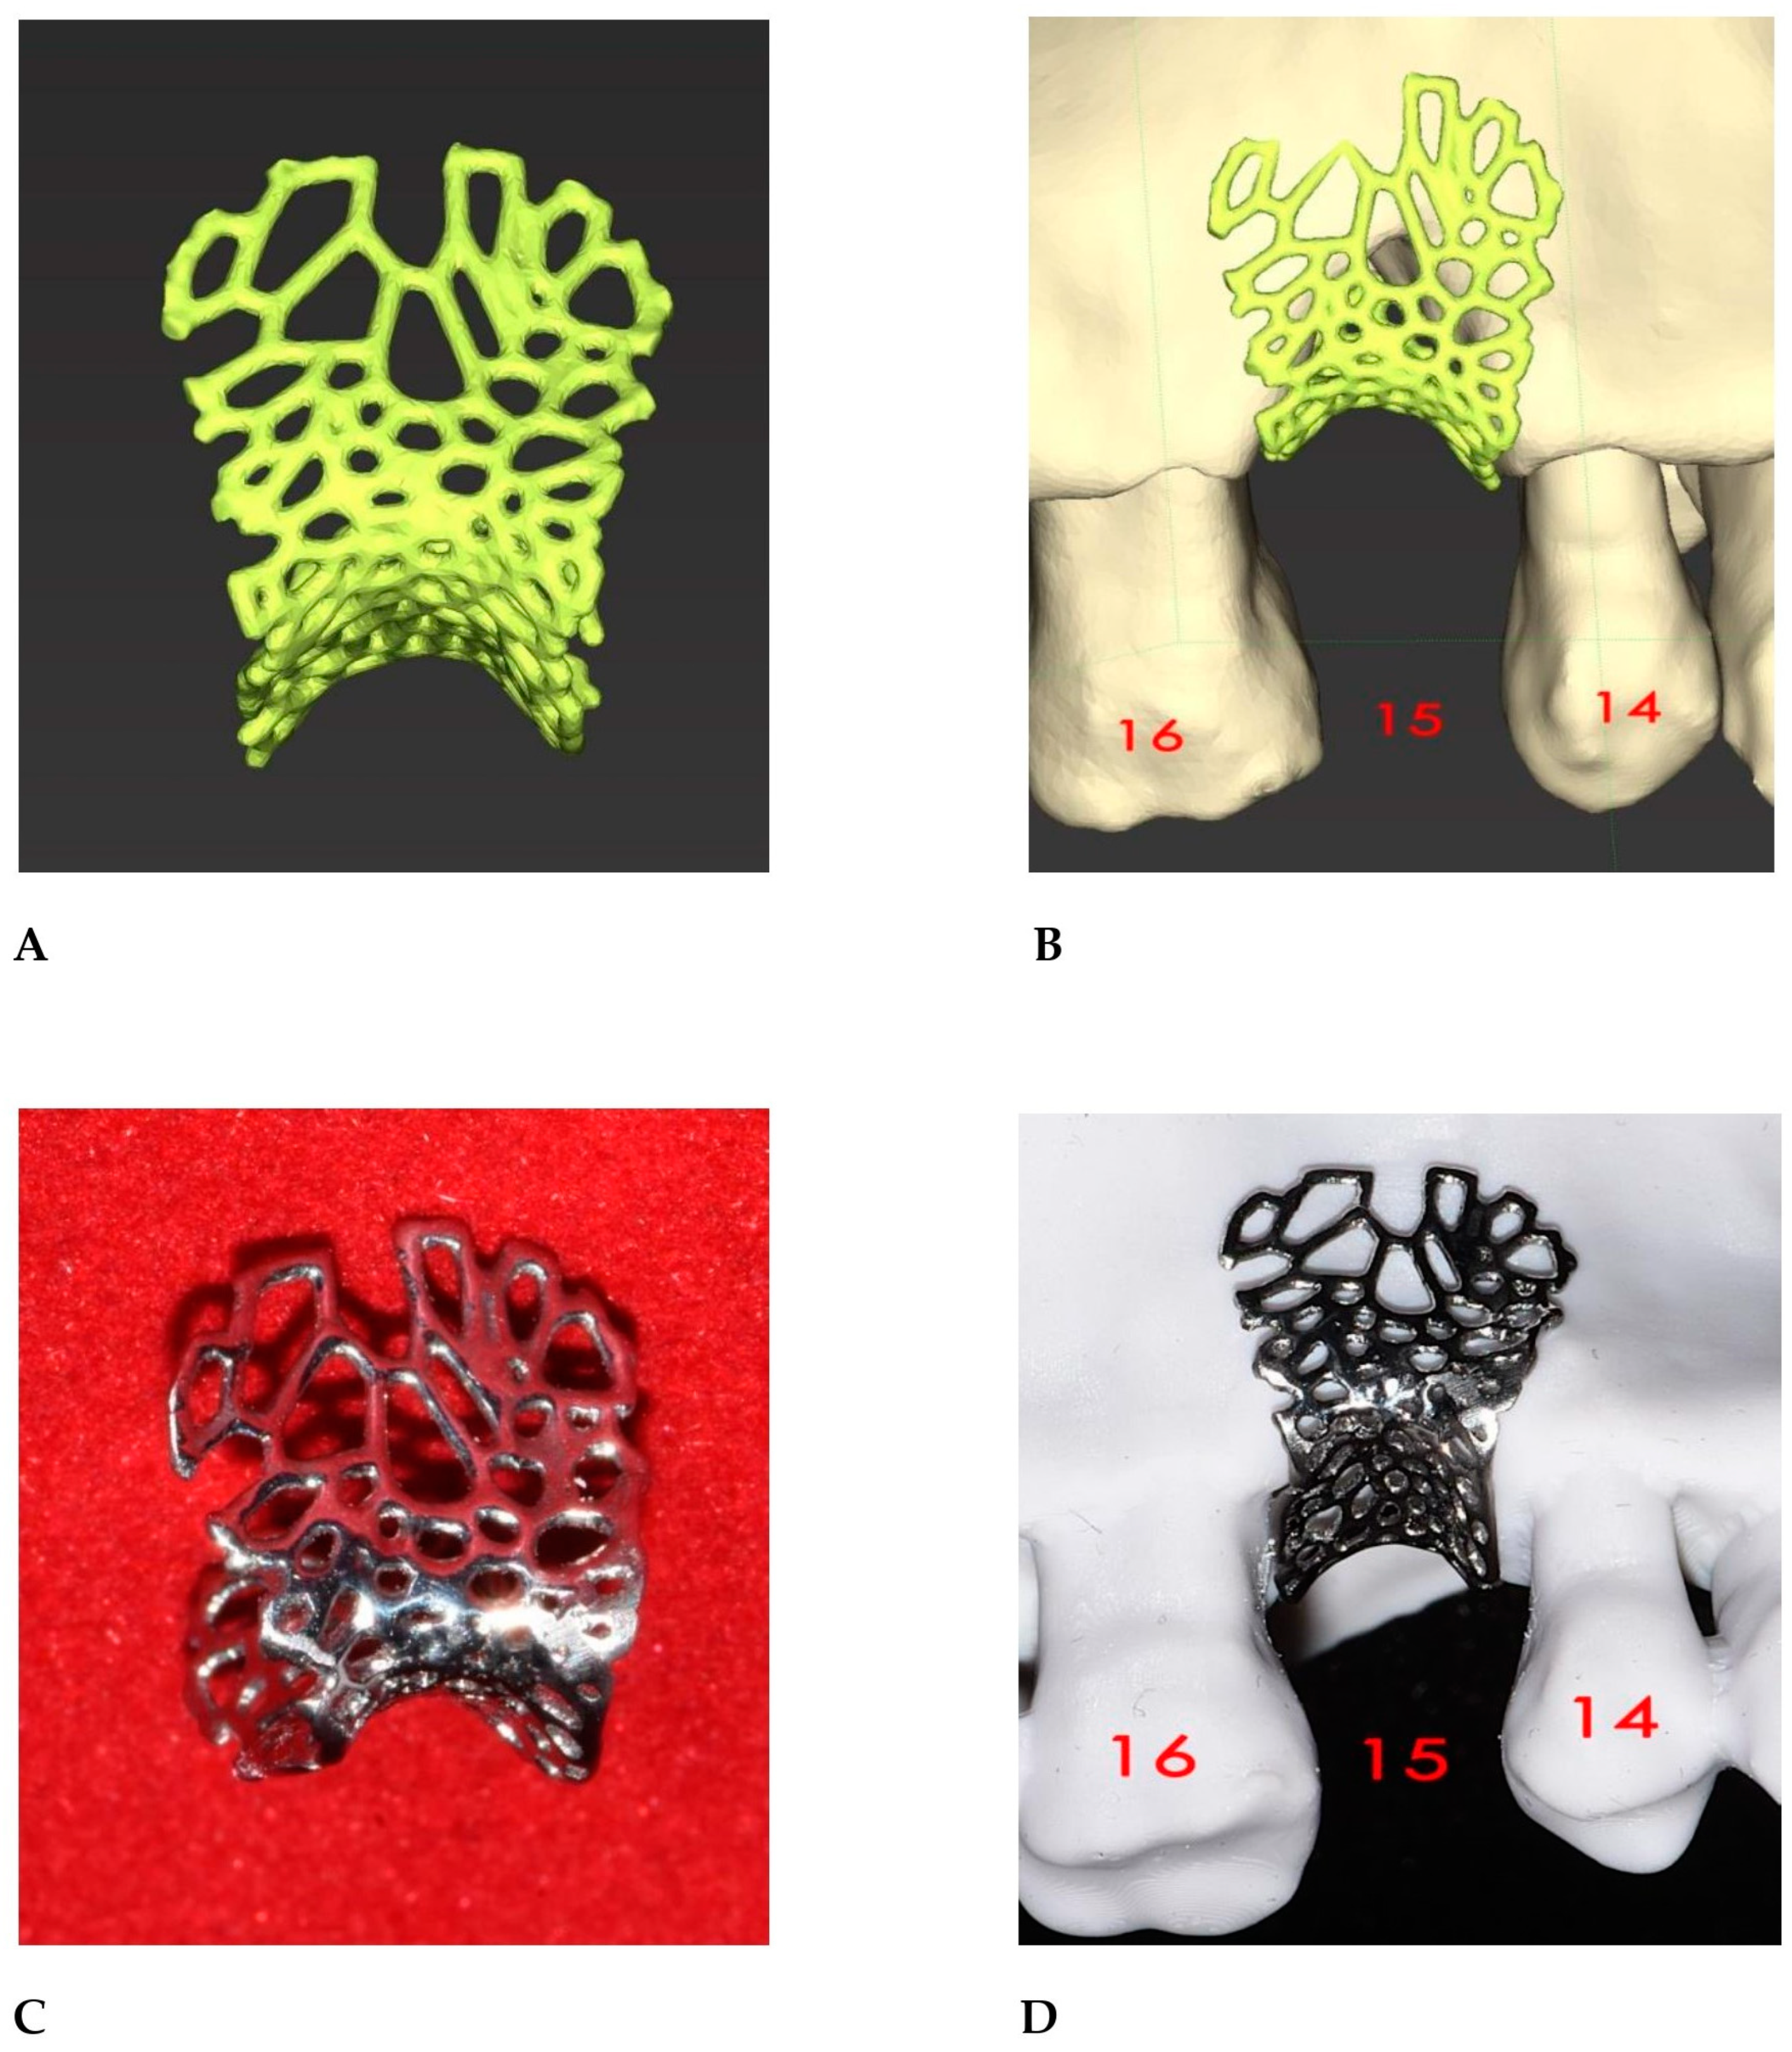

2.2. GBR Simulation and Mesh Design

3. Results